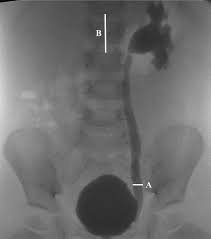

Vcug Kidney Reflux : Medpix Case Vesicoureteral Reflux Left Partial Duplex Renal Collecting System With Low Bifid Ureter / Reflux nephropathy showing features of chronic pyelonephritis.. Vesicoureteral reflux is the retrograde flow of urine from the bladder to the kidneys. Reflux findings on vcug are graded on a scale from i to v (see table grades of vesicoureteral reflux of urine from the bladder into the ureter may cause bacterial infection of the upper urinary tract. Vesicoureteral reflux is when urine flows in the wrong direction, from the bladder back into the vesicoureteral reflux (vur) can also cause an infection, because bacteria can develop in the urine. Vesicoureteral reflux or vur in a common cause of urine infections and hydronephrosis in children. Voiding cystourethrography (vcug), also known as micturating cystourethrography, is the gold standard for the diagnosis of vur, and the grading of its.

This is called vesicoureteral reflux or vur. What is vesicoureteral reflux (vur)? 986 likes · 1 talking about this. Separate pelves and ureters) • contrast seen only in the lower pole because that is the only ureter that has reflux. Copelovitch l., warady b.a., furth s.l.

Vur can increase the risk of a kidney uti (also called pyelonephritis). Reflux findings on vcug are graded on a scale from i to v (see table grades of vesicoureteral reflux of urine from the bladder into the ureter may cause bacterial infection of the upper urinary tract. The kidneys produce urine, which travels down tubes called the ureters. Hey guys today is the second day of tests for my son's kidney reflux. This is a particular risk if. Reflux nephropathy showing features of chronic pyelonephritis. Kidney reflux doesn't have symptoms, but urinary tract infections do. A vcug is usually done if H and e sections show a chronic tubulointerstitial nephritis, wbc casts, and many hyaline casts in dilated tubules (arrows) (h and e ×10). Vur can increase the risk of a kidney uti (also called pyelonephritis). What is vesicoureteral reflux (vur)? This is called vesicoureteral reflux or vur. The vcug looked great and i was feeling fine.